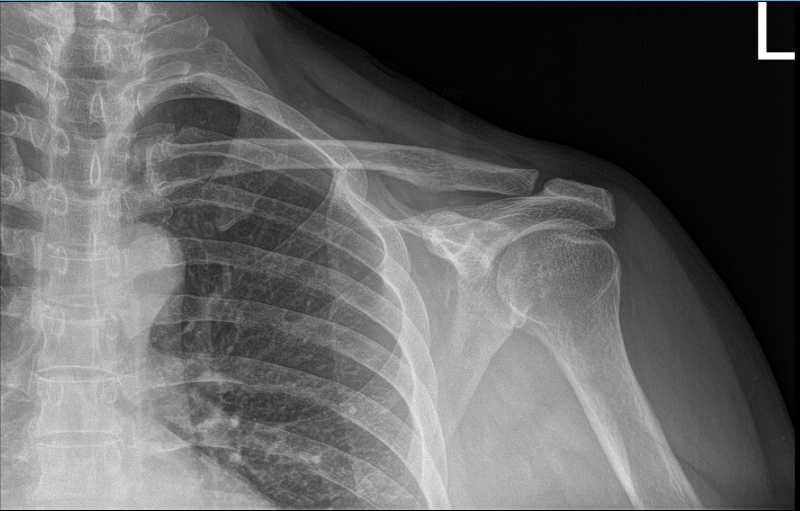

The patient presented today is a 66-year-old, male, and involved in a motor vehicle accident. He complained today about his bilateral shoulders, but the most painful one is his left shoulder. Patient had no shoulder pain prior to the car accident.

He has been doing therapy and it helped marginally. We suspected that the patient had a rotator cuff tear, however his Xray showed normal radiographs. So, we highly recommended that we take an MRI.

His MRI showed clear mild acromioclavicular hypertrophic change. MRI also showed rotator cuff tear of the supraspinatus along with a tear of the long head of biceps.

MRI of left shoulder